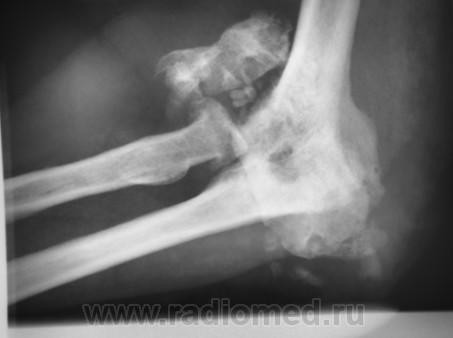

КСС. Артропатия. Сирингомиелия. +

Артропатия.  Сирингомиелия.

Продолжение.